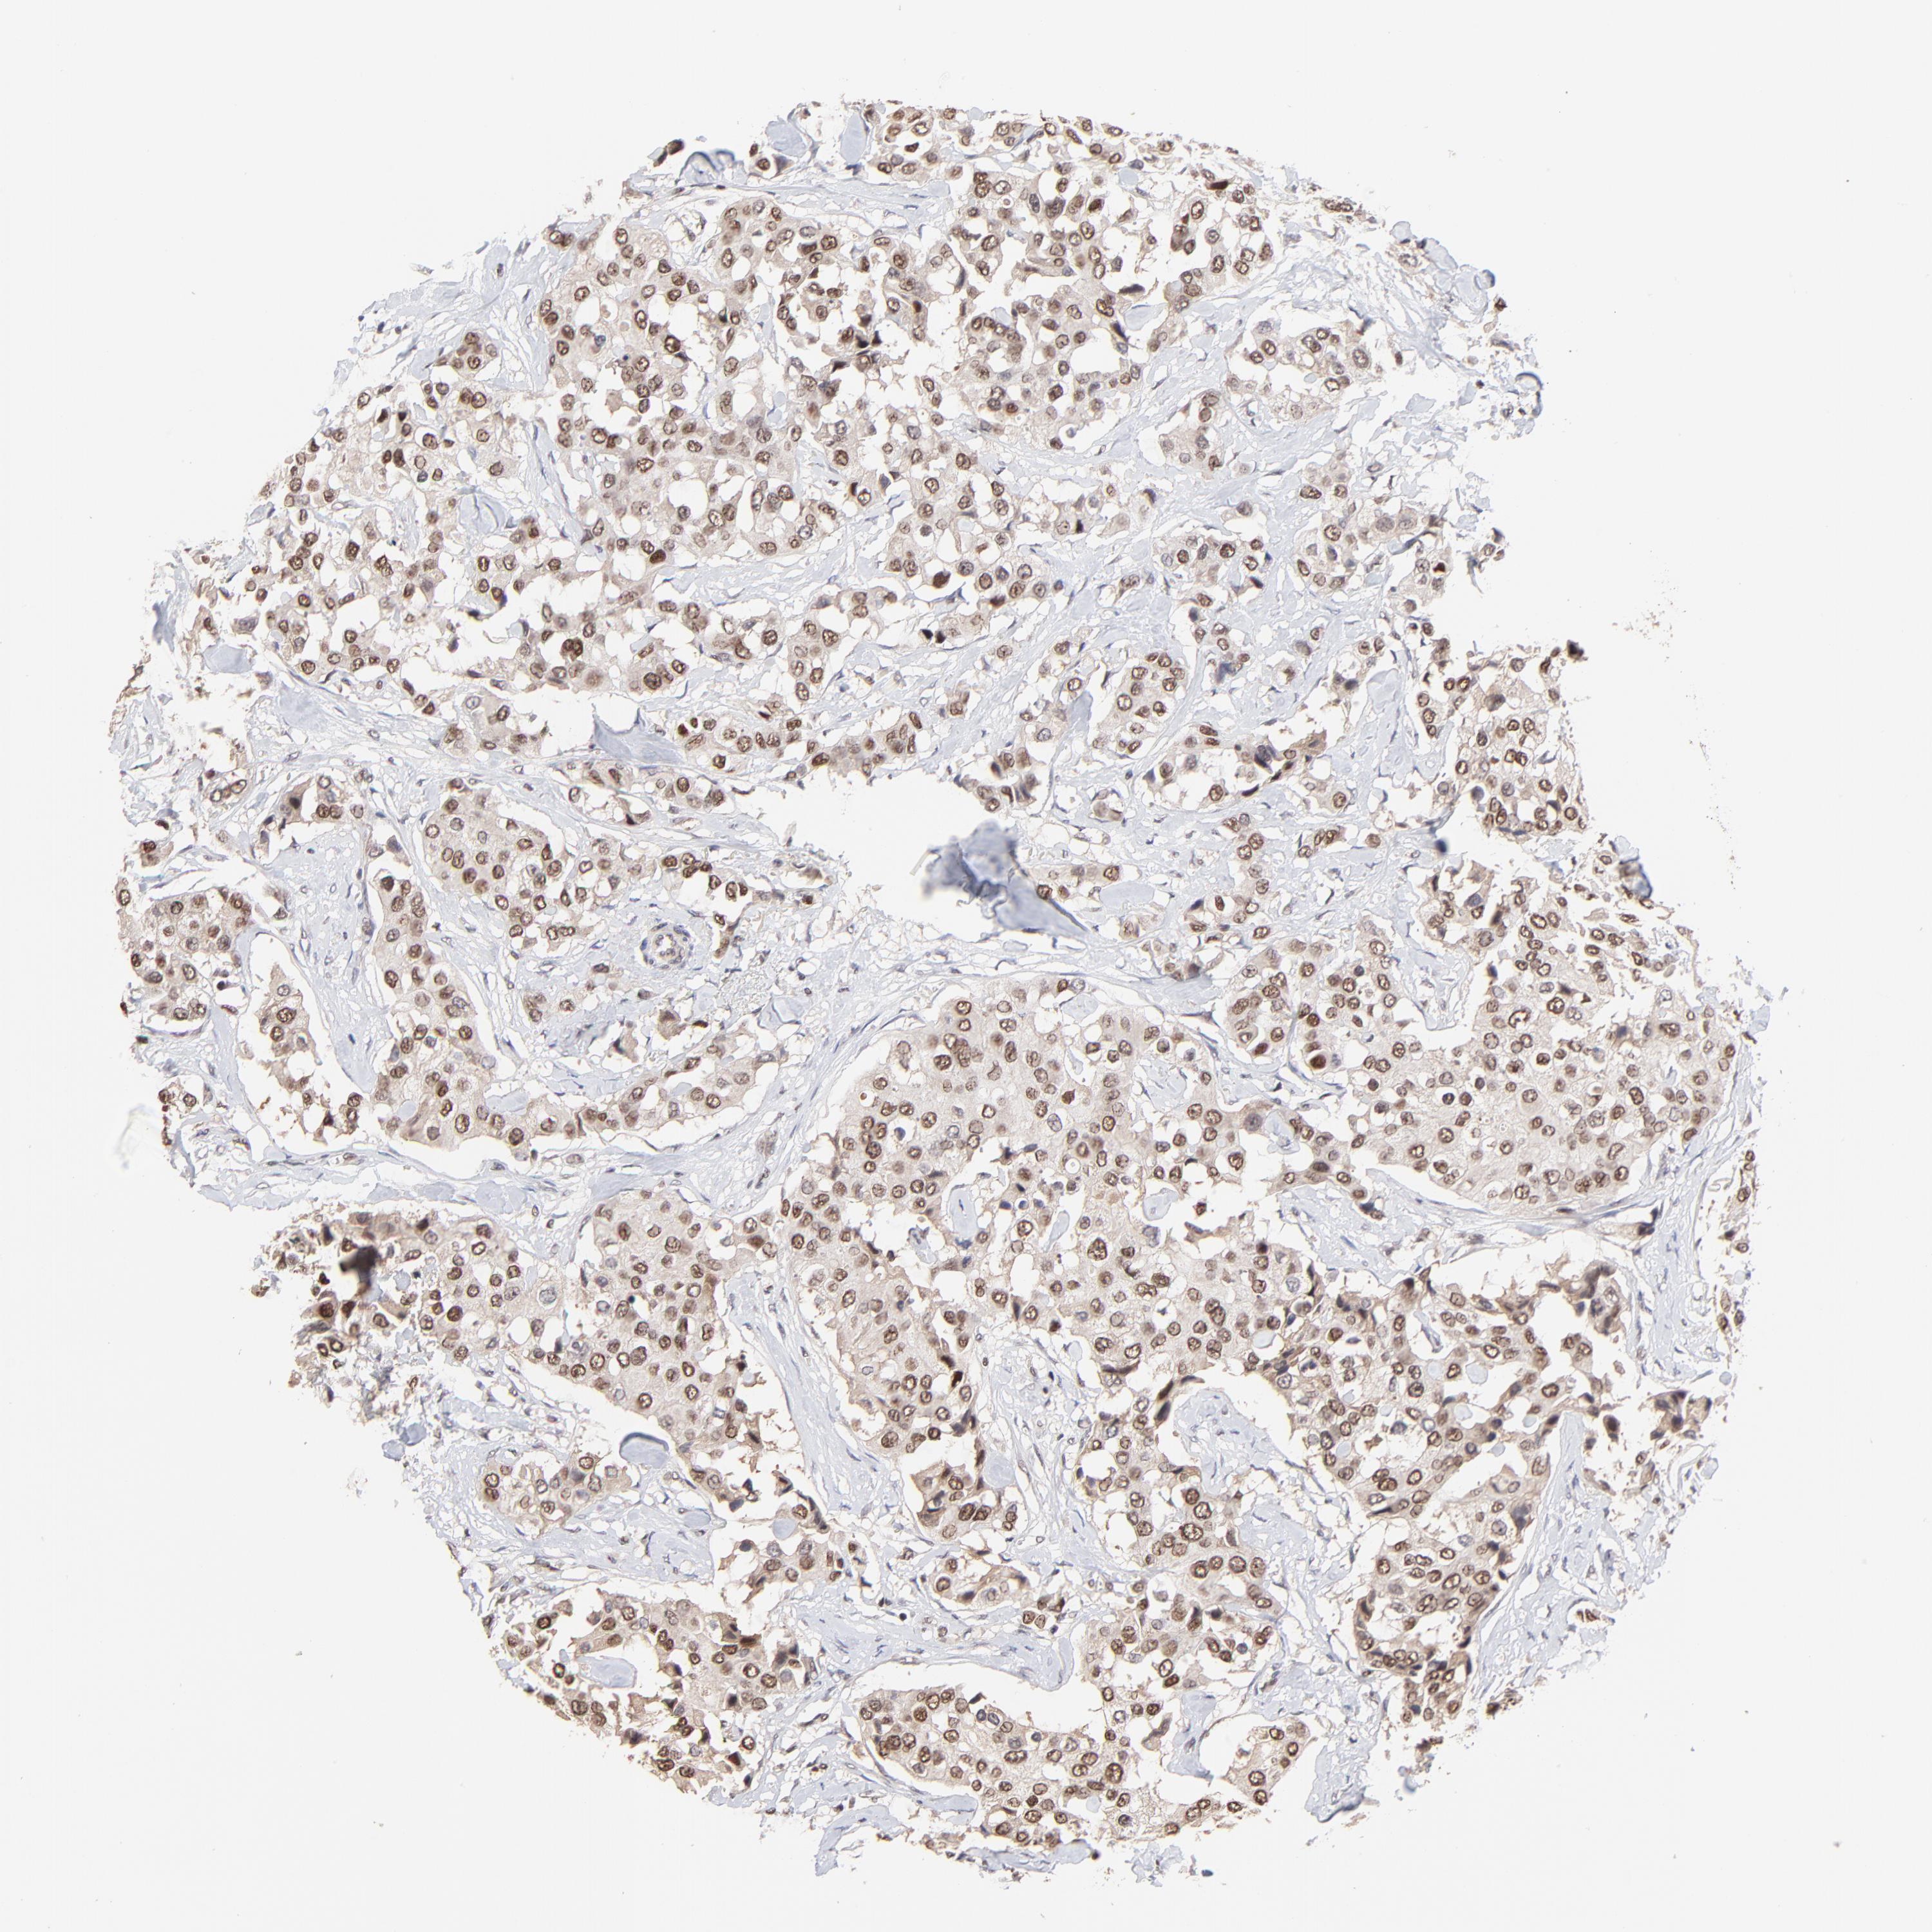

CANCER BREAST CANCER Show tissue menu

BRCA TCGA BRCA VALIDATION PROTEIN EXPRESSION

ANTIBODIES

AND

VALIDATION